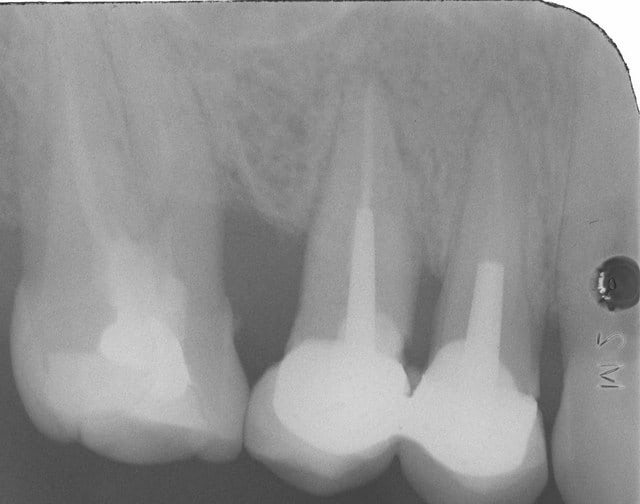

Suite a la demande de HODINA:

j ai retrouvé un autre cas d'extraction réimplantation .

extraction 2004

controle 2006

je peux convoquer la patiente pour radio si vous voulez voir 2014. ce qui est sur ç est que les dents sont tjs en bouche.

d'ailleur il faudrait que je le fasse car j avais scellé les 2 coiffes solidarisées au temp-bond.Je n avais pas pu les enlever par la suite.erreur.

2004 eic2ap - Eugenol

2006 beu3qo - Eugenol